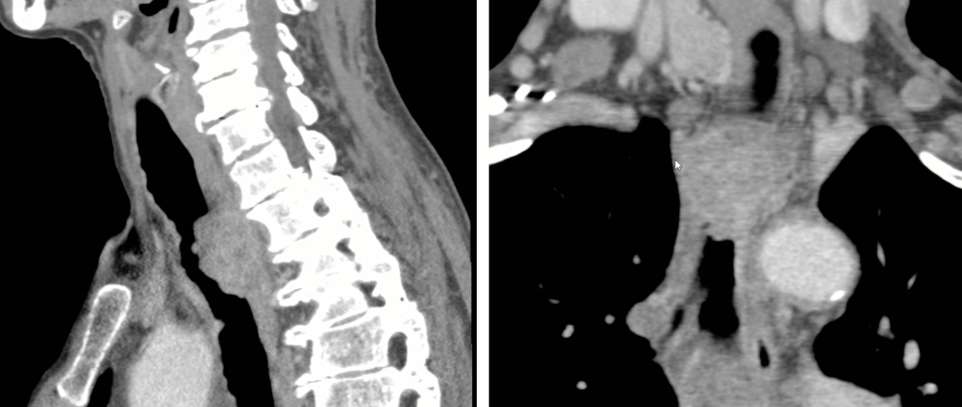

Sténoses Post-Infectieuses

- Post Tuberculose ++, lésion chronique

- Sur Médiastinite fibrosante

- Sténoses souvent étendues ou multifocales

- Souvent le TTT ATB ne suffit pas et il faut dilater

Schwannome

Schwannome

Tumeur trachéale

Tumeur trachéale

Mesures Utiles

- Distance aux cordes vocales

- Longeur de la sténose

- Distance à la carène